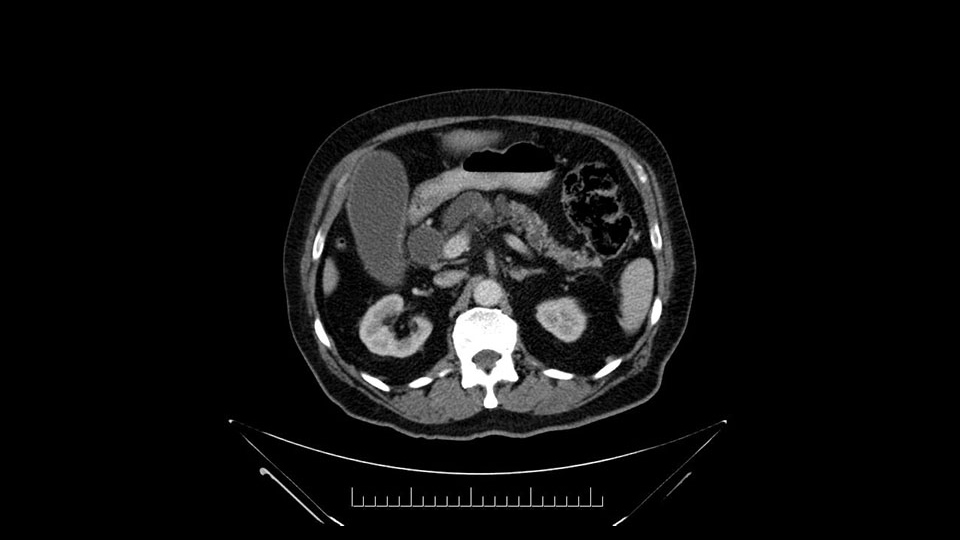

He has no liver metastases or obvious metastatic disease. On reviewing his CT scan, he has normal vascular anatomy; he has no involvement of the portal vein by the looks of it, or the superior mesenteric vein.

He has normal arterial anatomy: no accessory or replaced right hepatic artery, which is important because sometimes the right hepatic artery can come behind the neck of the pancreas and you have to be careful of that in a Whipple dissection.

Anyhow. What the surgeon does need to do though, is focus on the resection. What I generally do is look at the tumor, which is here, and then I look at the nature of the pancreas. That’s really just to get an idea on what it would be like to do the pancreatic anastomosis, which isn’t technically the biggest deal, but it’s the biggest deal for the patient afterwards; and the larger the duct and the harder the pancreas, the less likely it’s going to leak. Leaks are what cause almost all the morbidity so I do think of it mentally. I wouldn’t do anything differently, the night before or the morning or the surgery or during the surgery, but certainly mentally it’s useful to know that you may have a challenge in terms of doing the best pancreatic anastomosis you can. I think the duct is quite large. The interesting thing about the duct: it does peter out into fairly normal looking pancreas; that’s a bit strange. But I’ll assume the duct is large.

The next item that I would look at: the issue would be the vessels and usually start at the portal vein, watch the portal vein, follow it down, down-down-down to the neck of the pancreas - which is here - and there’s no impingement by tumor, which is great. The SMV and the splenic vein, which is here. The splenic vein junction is normal, which is great.

Looking at the C.T. scan, the most important thing to determine is, of course, does the patient have any evidence of metastatic or disseminated disease or locally advanced disease? The imaging shows dilated intrahepatic biliary tree but I don't see any signs of liver metastasis. As would be expected with a ampullary lesion there's no evidence of major visceral vessel invasion. So this patient would look to me to be a candidate for pancreaticoduodenectomy or Whipple procedure.

The first steps of a pancreaticoduodenectomy involve ensuring the CT findings are correct: exploring for signs of metastatic disease, peritoneal implants involving the omentum or the undersurface of the diaphragm and if again this is confirmed exploration that there's no metastatic disease, I begin the mobilization and really determining the relationship of the tumor with the major visceral vessels. I start by an extended Kocher maneuver, identify the superior mesenteric vein below the neck of the pancreas. They’re very thin walled vessels and as you're dissecting you have to use the ultimate care and meticulously dissect the superior mesenteric vein, ligate the anterior branches and begin the dissection from below to under the neck of the pancreas. At this point, if there's no reason to be concerned about whether there is any vascular invasion below, I usually take the gallbladder down. I mobilize the common hepatic duct above the insertion of the gallbladder. This patients already has a stent in place. So I would divide the bile duct at this point. This facilitates the dissection of the anterior surface of the portal vein and as I would expect looking at this imaging that there is nothing to be concerned about in terms of vascular involvement.